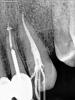

hauff Опубликовано 1 марта, 2013 Автор Поделиться Опубликовано 1 марта, 2013 Прикладываю снимок. Посмотрите, пожалуйста, как сидят коронки. Как уже говорил немного беспокоит десна между ними и 3-кой. Хотя возможно это связано с 3-кой. Ссылка на комментарий

hauff Опубликовано 2 марта, 2013 Автор Поделиться Опубликовано 2 марта, 2013 (изменено) Снимок добавил. Кто-нибудь ответит как сидят коронки? Спасибо за ответ! Изменено 2 марта, 2013 пользователем hauff Ссылка на комментарий

Prosthodontist Опубликовано 2 марта, 2013 Поделиться Опубликовано 2 марта, 2013 это проблема из-за клыка который вы лечите, полость на контактной поверхности! коронки сидят на 3, да еще и спаянные, через какое то время начнутся проблемы с десной Ссылка на комментарий

Prosthodontist Опубликовано 2 марта, 2013 Поделиться Опубликовано 2 марта, 2013 А мне тут сказали что вполне нормально сидят. А в чём проблема спаянности? Как-то по другому их обычно вместе собирают? И почему проблемы с десной обязательно начнутся?может для кого то и нормально, у каждого доктора свой критерий качества, плюс имеется протокол фиксации, который если ты не соблюдаешь, то практически при любой посадке могут быть проблемы.На счет спаянности коронок, обратите внимание, во рту у нас все зубы стоят раздельно друг от друга, природа придумала это не просто так, для спаяваня коронок, на это должны быть показания, в вашем случае я его не вижу, во всяком случае по этому снимку, просто либо доктор решил перестраховаться либо так проще сделать как технически, так и врачебно. это мк или цирконий? 1 Ссылка на комментарий